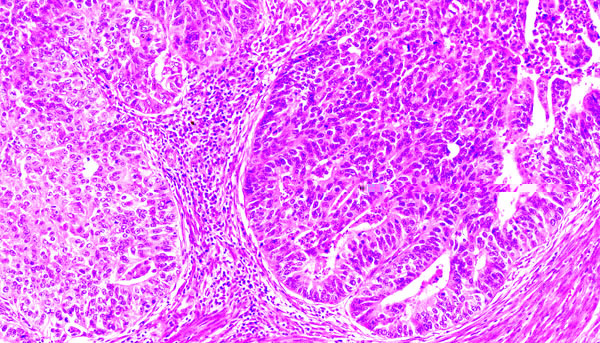

Adenocarcinoma of the uterus, grade 2

The tumors are composed of cells that form solid nests and only occasionally some glands.